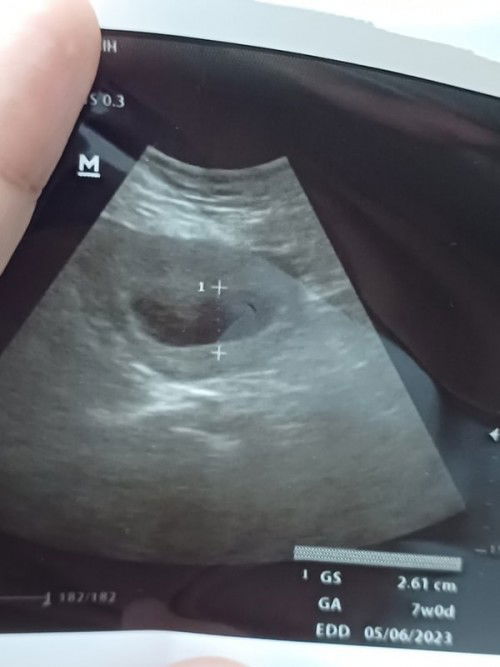

Hallo bunda.. aku hpht 24 agustus 2022 kmrn. Kalau hitungan dri hpht usia sudah 7w5d Cuma kemarin aku usg 2d janinnya belum terlihat. Hanya terlihat kantung janin yg ukurannya 7w. Tapi ga ada flek dan ada sedikit nyeri di perut kiri. Kira2 wajar ga ya bund? Takut blighted ovum aku... Mohon sharingnya bund#seriusnanya #bantusharing #ingintahu